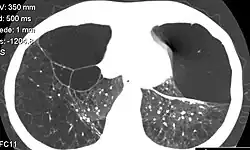

Emphysema due to alpha-1 antitrypsin deficiency

Computed tomography of the lung showing emphysema and bullae in the lower lobes of a subject with type ZZ alpha-1 antitrypsin deficiency. There is also increased lung density in areas with compression of lung tissue by the bullae.